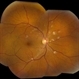

- Jason S. Calhoun, Department of Ophthalmology, Mayo Clinic Jacksonville, Florida

- Fundus camera

- Radioactive retinopathy present with hard exudates at 11 o'clock in the right eye. Patient had radioactive implant surgery.